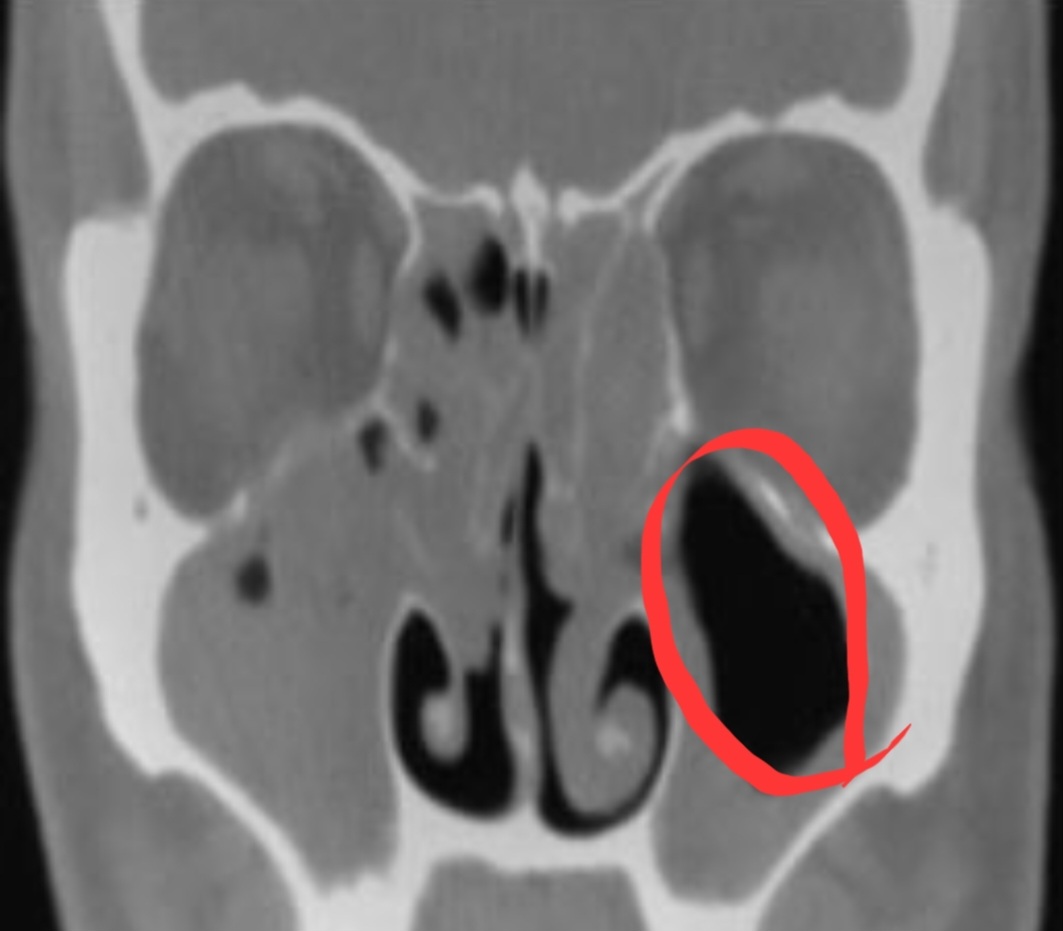

▶ 위 사진 분석

1) 첫 번째 사진: 코 옆 빨간색 동그라미 친 부분

-> 빨간색으로 표시한 부분이 있지요? 첫 번째 사진 보시면 코 옆쪽에 검은색 부분이 있는데 이곳이 바로 부비동입니다. 고름이 차 있으면 저 검정색 부분이 회색으로 보입니다.